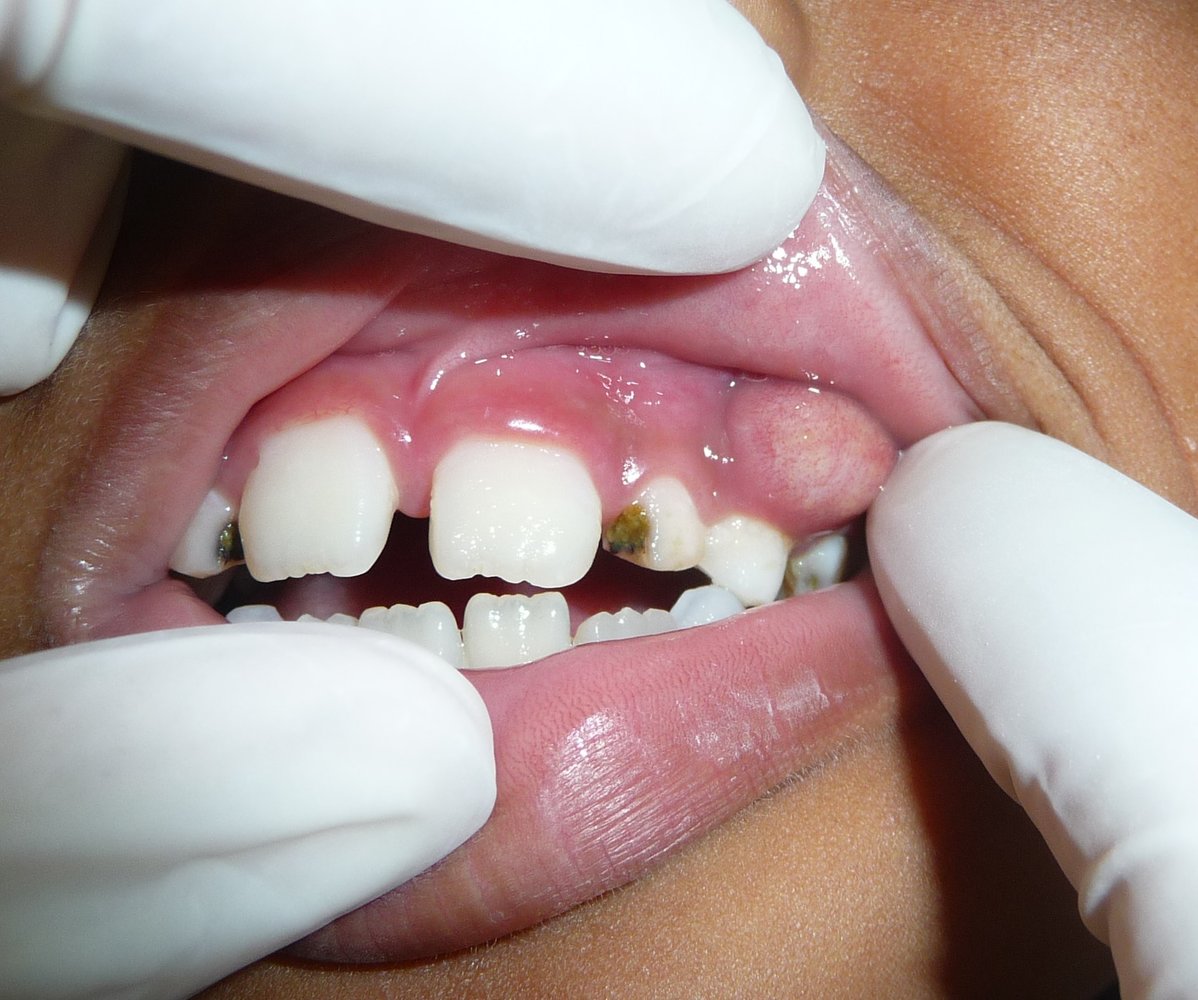

• Clinical features

• Tooth pain

• Possibly bad breath

• Inspection of the oral cavity with a mouth mirror: change in enamel (e.g., enamel breakdown, surface discoloration)

• The teeth can be probed with dental instruments to check for soft areas.

• Bitewing radiography: Carious lesions appear radiolucent.

• Treatment: depends on the size and extent of the lesion

• Very small lesion in which remineralization is still possible: The application of fluoride gel, varnishes, pit, and/or fissure sealant usually suffices.

• Lesions that involve hard tissues but do not involve the pulp: caries excavation and restoration of the dental surface

• Lesions that involve both enamel and dentin in proximity to the pulp: indirect pulp capping

• Lesions that involve enamel, dentin, and pulp: root canal treatment, followed by extracoronal restoration